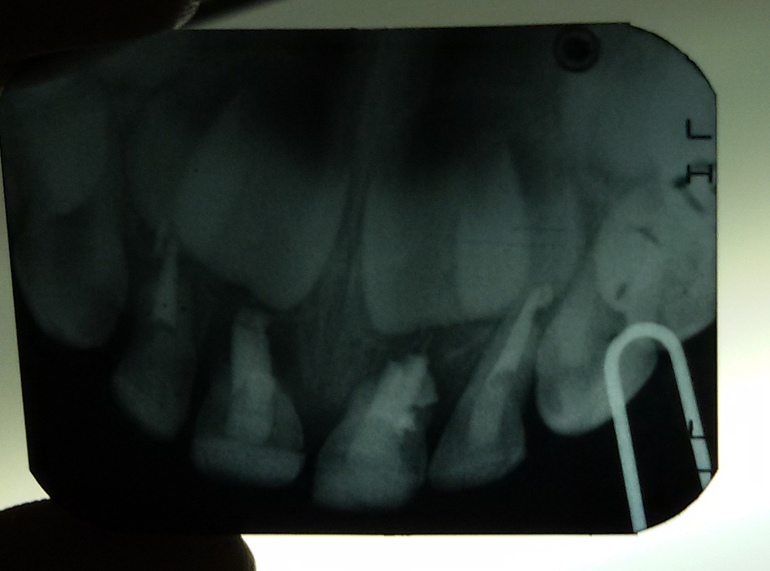

Скажите, пожалуйста, можно ли спасти зубки дочке. Ей 3 года, около 1,5 лет назад мы лечили пульпиты на передних зубах, а недавно стукнулись ими. И вроде бы не сильно, но зубки, верхние единички, начали шататься. Сейчас над одним появился свищ, как сказал стоматолог, к которому ходили. Сделали снимок, прилагается, нам сказали, что удалять оба надо. Но нам очень не хочется, тогда не удалили и сейчас не хотим. Скажите, есть какая-нибудь возможность сохранить, может лечение? Очень хочется спасти.

Здравствуйте.Я соглашусь с Вашим стоматологом о том, что зуб нужно удалять. Зубы держатся в кости практически одним материалом, которым пломбировали каналы. Корень рассосался ( это физиологическое действие), пломбировочный материал рассасывается тоже.Можно было бы расшатывать самим, все равно Вы сможете лишиться зубов и дома, если бы не наличие свища, что диктует чуть скорую эвакуацию зубов.Не переживайте) Организм сам так решил. Корни-то зубов рассосались)

Вторые удалять пока не надо, у них еще довольно длинные корни, но тоже уже начали рассасываться.Никаких ортодонтических вмешательств не требуется.